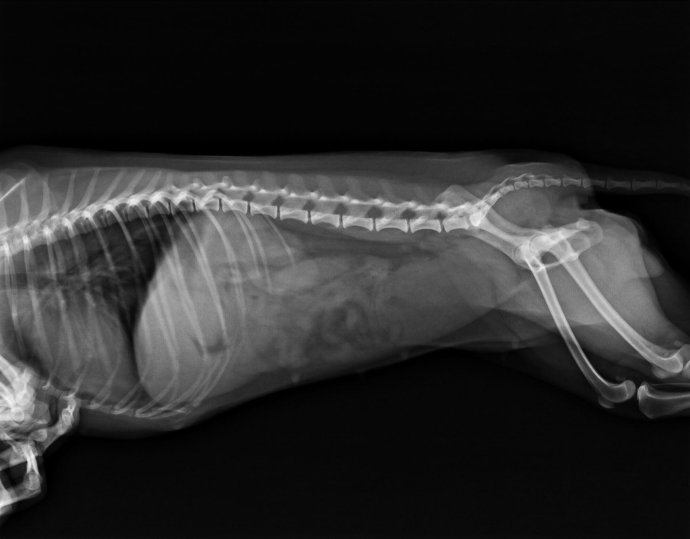

临床检查该犬精神沉郁,不愿动,触诊腹部的胃和小肠区敏感。结膜颜色粉红,体温39.5摄氏度。心音心率正常。怀疑胃肠道异物或胰腺炎,检查CBC/CPL,结果胰腺炎阴性,WBC 3.6*109/L,中性粒细胞数目降低,其他正常。拍CR平片如下:

CR结果如下: